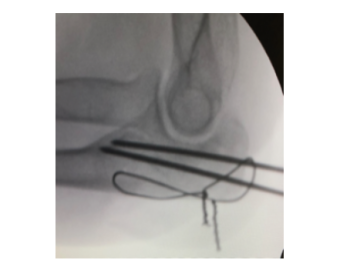

Ayak Bileği 4322 OkunmaDirsek

Dirsek - Yapım Aşamasında

Dirsek 12580 OkunmaAmeliyat sonrası nasılsınız?